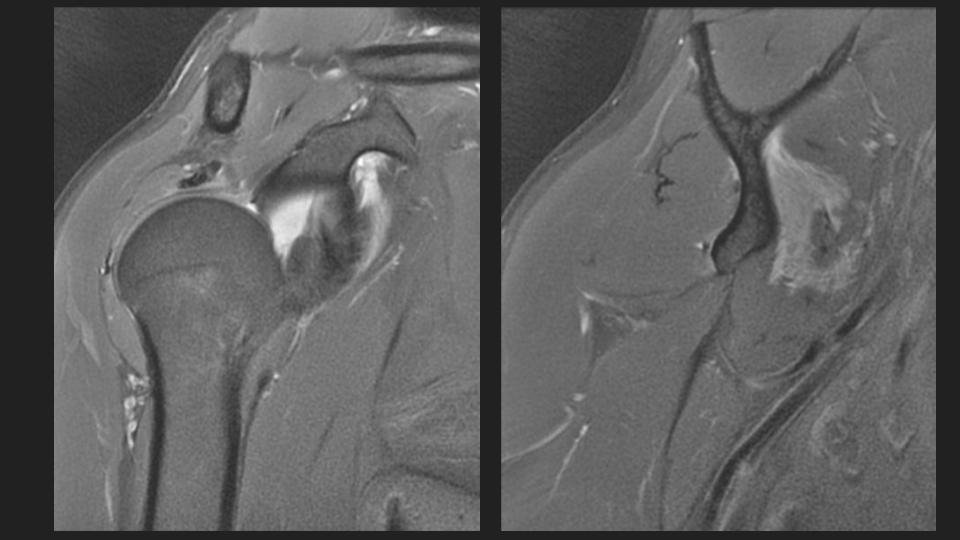

36M with chronic pain and limited motion 3 years after work related injury

My colleague had to share this with me after a failed attempt at arthrography. He puts the shoulder in Grashey, but it doesnt really look like Grashey. No matter what, he couldnt get in and converted it to a routine MRI. The first set of Cor images look so nice....or do they? The crazy thing is that the injury was 3 years ago. Not all workers comp is bogus. I was taught the posterior shoulder dislocation locks the shoulder in internal rotation, but based on the axial image, it is not. 1) Why is that? 2) I think thats partly why the scout image for the arthrogram was so misleading.

dislocation ( RID4770 )